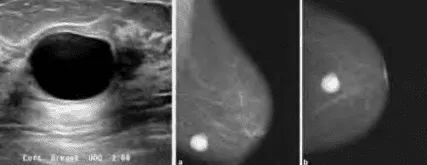

Phần tiêu đề “Cận lâm sàng”Hình ảnh “Nang vú trên siêu âm: (Trái) nang điển hình: phản âm trống, bóng lưng rõ; (Phải) nang không điển hình: vách dày, cặn lắng”.

Siêu âm:

- Nang điển hình: Khối dạng tròn/bầu dục, bờ mỏng, phản âm trống (anechoic), bóng lưng (posterior acoustic enhancement), không có thành dày hay chồi nội dịch.

- Nang không điển hình (complicated cyst): Có vách dày, cặn lắng bờ dưới, không hoàn toàn bóng lưng. Cần chọc hút hoặc theo dõi chặt.

Nhũ ảnh:

- Nang xuất hiện dưới dạng vùng đậm độ thấp (hypodense), giới hạn rõ, không vôi hóa.

- Đôi khi không phân biệt rõ nang đặc - đặc biệt nang nhỏ < 5 mm.